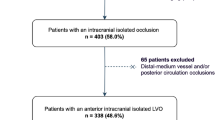

A total of 964 patients with acute ischaemic stroke were screened between January 2017 and December 2019, of whom 770 patients underwent TOF MRA imaging. Sixty-seven patients were excluded because arterial feature extraction was unavailable due to poor image quality. We also excluded 65 patients with vascular anomalies other than atherosclerosis, such as dissection, Moyamoya disease, and reversible cerebral vasoconstriction syndrome, and 122 patients with major intracranial arterial occlusion (Fig. 1). Of the 516 participants (mean age 67.6 ± 13.0 years, 34.9% women) included, 274 patients had no ICAS, 140 patients had one ICAS (low ICAS burden), and 102 patients had two or more ICAS (high ICAS burden). The high ICAS burden group was older and had more comorbidities, such as hypertension, diabetes mellitus, and coronary artery disease. Details of the participants are summarized in Table 1.